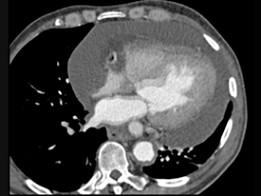

问题 男,28岁,胸闷气急,伴干咳,查体见颈静脉显露,CT如图,最可能的诊断为 ( )

选项 A、贫血性心脏病 B、心包转移瘤 C、心包积液 D、心肌炎 E、心包肥厚

答案 C